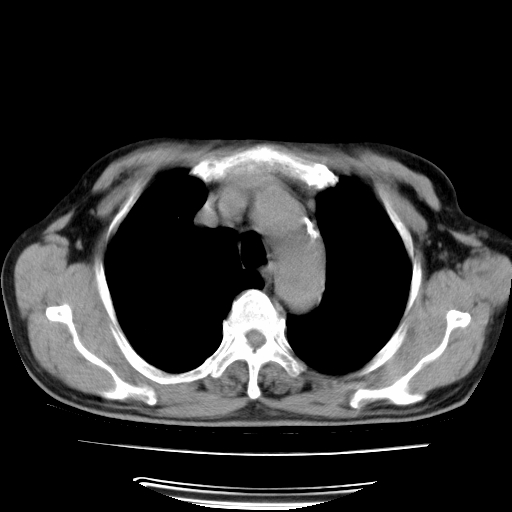

男,71岁,咳嗽,气喘10年,再发并咯血.胸片见气胸

考虑  左肺中心型肺癌伴阻塞性肺炎,肺不张,纵膈淋巴结肿大。慢支炎,肺气肿,左侧气胸肺压缩5%

左侧中央型肺癌伴纵膈淋巴结转移。

左肺中心型肺癌伴阻塞性肺炎,肺不张,纵膈淋巴结肿大

1)考虑左肺中心型肺癌伴阻塞性肺炎、左肺下叶肺不张、左侧肺气肿,纵膈淋巴结转移。2)左侧气胸(肺组织压缩约5%)。

左肺中心型肺癌伴阻塞性肺不张、肺气肿 。

1)考虑左肺中心型肺癌伴阻塞性肺炎、左肺下叶肺不张、左侧肺气肿,纵膈淋巴结转移。2)左侧气胸。